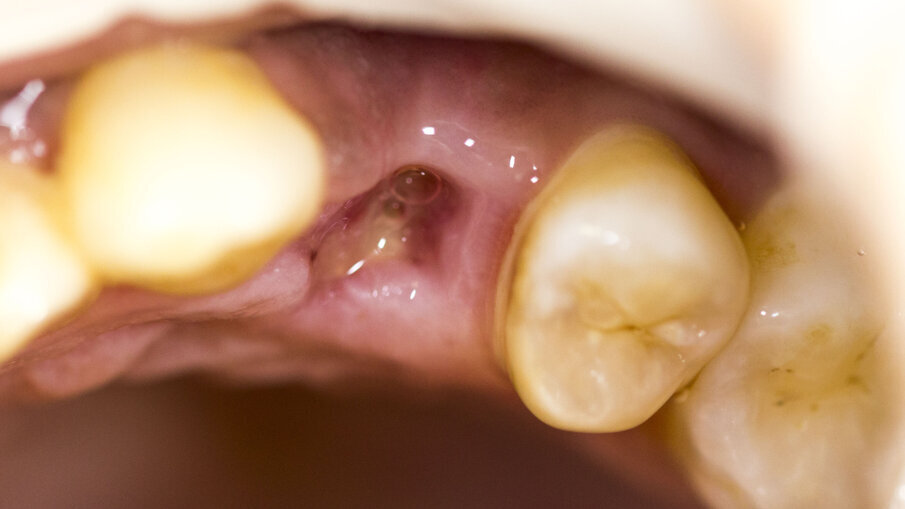

Fig. 9 - Situazione dopo sei giorni.

Fig. 10 - Rimozione della sutura dopo sei giorni.

Fig. 11 - Situazione due settimane dopo: buona guarigione senza interferenze da parte del biomateriale.